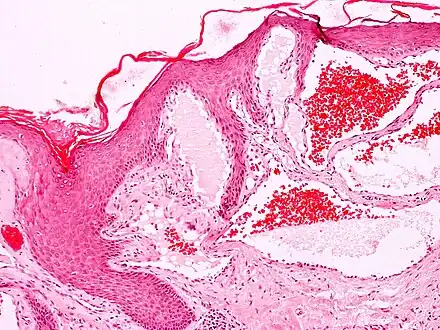

Angiokeratomas characteristically have large dilated blood vessels in the superficial dermis and hyperkeratosis (overlying the dilated vessels).

Scrotal angiokeratoma; visible large dilated blood vessels and hyperkeratosis- Scrotal angiokeratoma (Fordyce type); multiple papules made by dilatated capillaries

- Scrotal angiokeratoma (Fordyce type); dilated cavernous capillaries, acanthosis